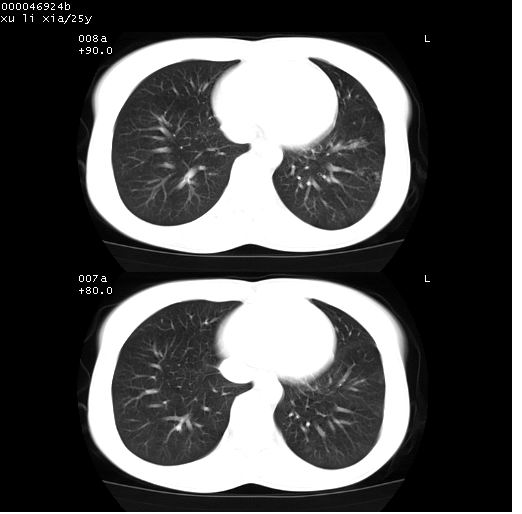

患者 女,25岁。因“左侧卵巢肿瘤”术前胸片偶然发现两肺病变。平素无明显不适,无呼吸系统症状及体征,无传染病史。

胸部ct轴位平扫(层厚10mm,螺距1.5,重建间隔10mm),图像如下:

病灶呈地图样分布于肺外围,与正常组织分界清晰+弥漫性磨玻璃影中见小叶间隔增厚呈碎石路样表现+年轻女性,无明显临床症状=肺泡蛋白沉积症?

双肺病灶以渗出影搀杂斑点状阴影为主,部分阴影融合成团片,并沿纹理明显见播散灶。支持楼主:两肺感染性病变(结核可能性大)!

病灶呈离心性分布,以两上肺多见,远离肺血管纹理,有部分肺间质条索影,病人症状轻微,考虑结节病。

平行于间质走行微结节影;拌钙化灶;分布通气好的肺野